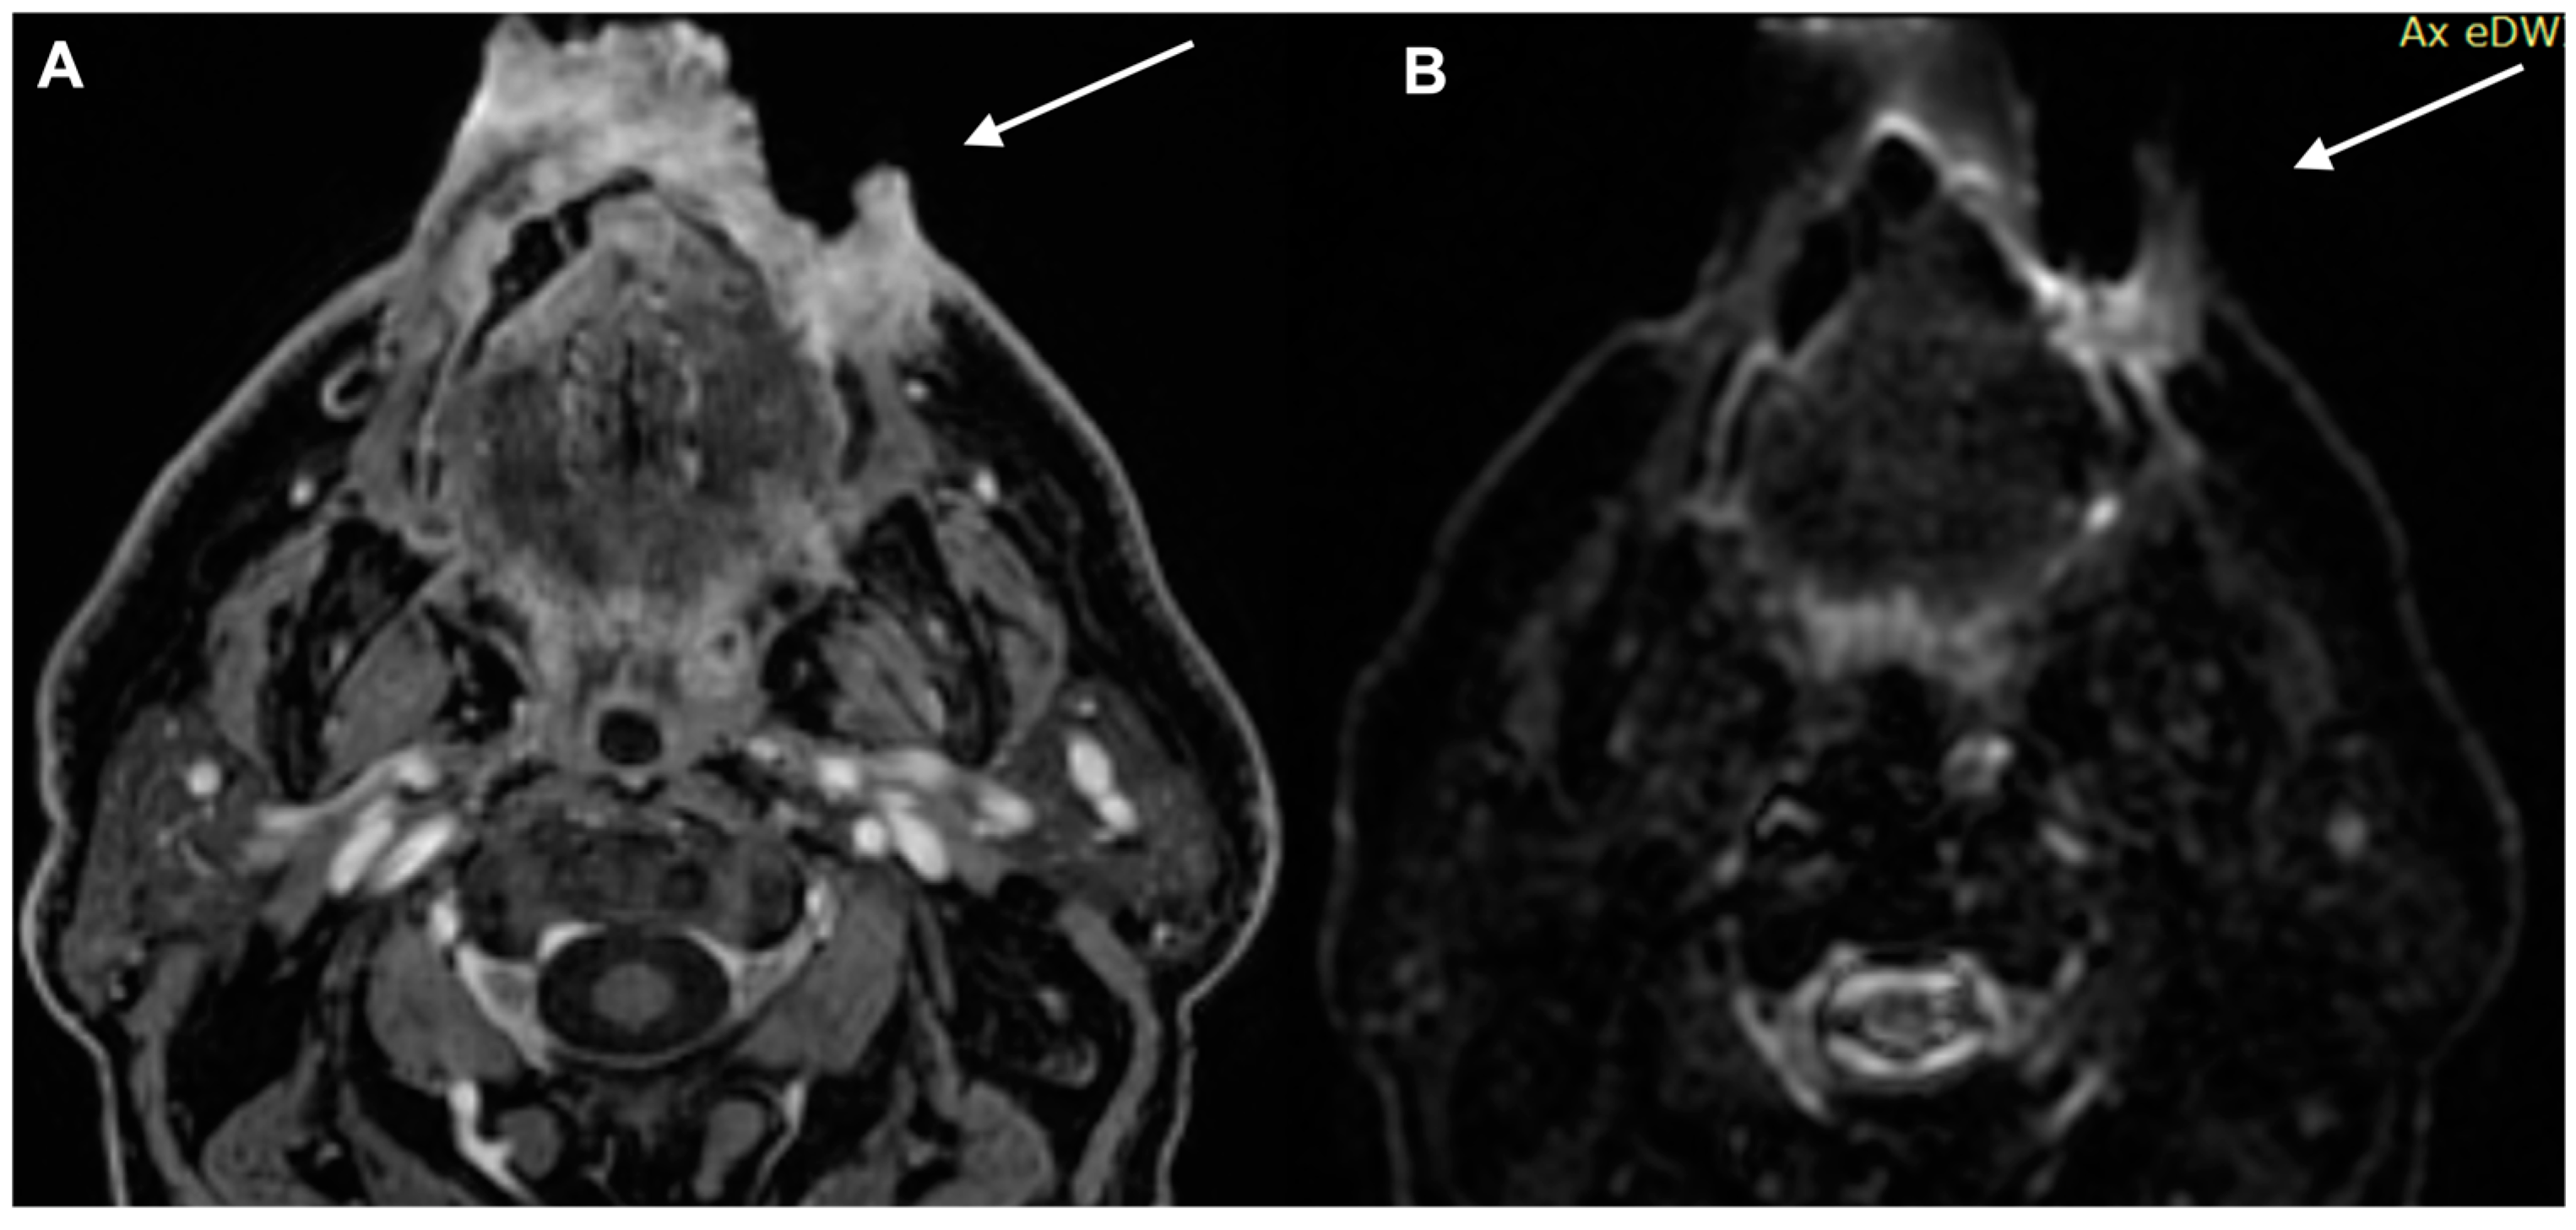

- Kawaguchi, M.; Kato, H.; Noda, Y.; Kobayashi, K.; Miyazaki, T.; Hyodo, F.; Matsuo, M. Imaging findings of malignant skin tumors: Radiological–pathological correlation. Insights Imaging 2022, 13, 52. [Google Scholar] [CrossRef] [PubMed]

- Kawaguchi, M.; Kato, H.; Suzui, N.; Miyazaki, T.; Tomita, H.; Hara, A.; Matsuyama, K.; Seishima, M.; Matsuo, M. Imaging findings of cutaneous angiosarcoma of the scalp: Comparison with cutaneous squamous cell carcinoma. Neuroradiol. J. 2021, 34, 329–334. [Google Scholar] [CrossRef]

- Kawaguchi, M.; Kato, H.; Tomita, H.; Hara, A.; Suzui, N.; Miyazaki, T.; Matsuyama, K.; Seishima, M.; Matsuo, M. Magnetic Resonance Imaging Findings Differentiating Cutaneous Basal Cell Carcinoma from Squamous Cell Carcinoma in the Head and Neck Region. Korean J. Radiol. 2020, 21, 325–331. [Google Scholar] [CrossRef] [PubMed]

- Kawaguchi, M.; Kato, H.; Tomita, H.; Hara, A.; Suzui, N.; Miyazaki, T.; Matsuyama, K.; Seishima, M.; Matsuo, M. MR imaging findings for differentiating cutaneous malignant melanoma from squamous cell carcinoma. Eur. J. Radiol. 2020, 132, 109212. [Google Scholar] [CrossRef] [PubMed]